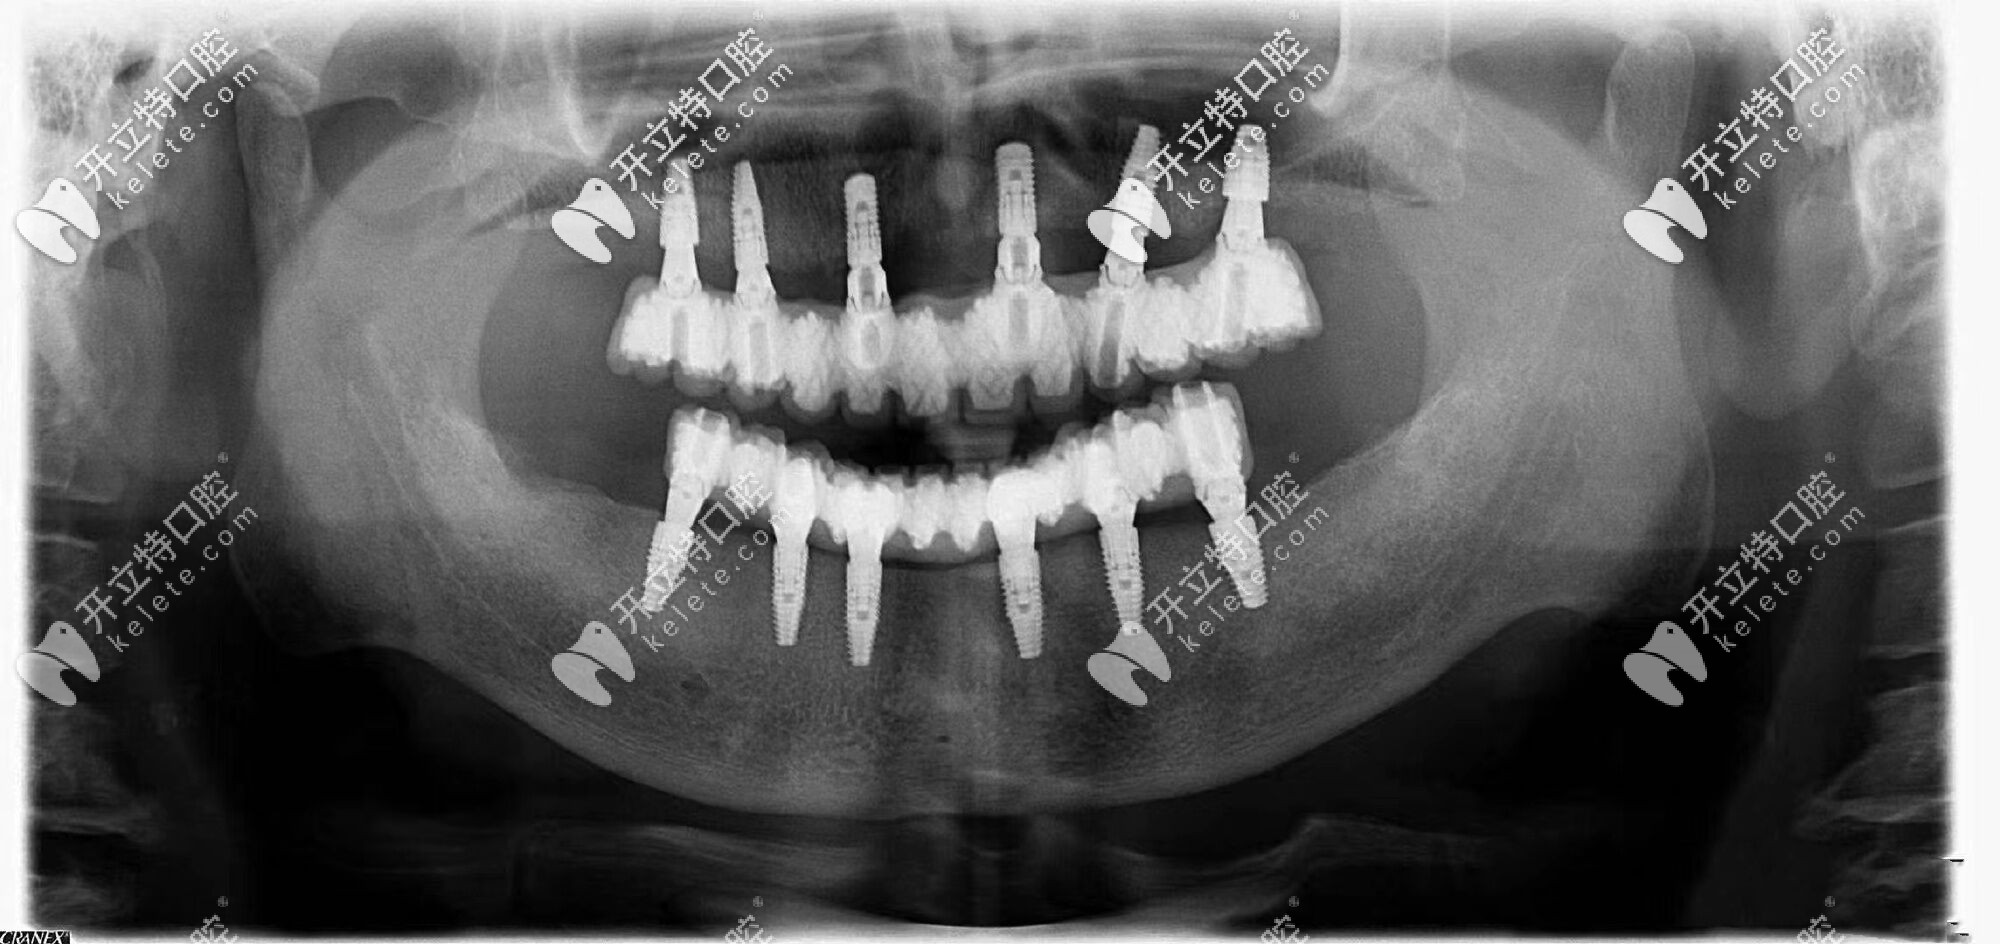

由于常年戴活動(dòng)假牙,導(dǎo)致自身牙槽骨的條件較差,醫(yī)生給張叔設(shè)計(jì)了全口即刻種植牙的方案,沒想到3個(gè)小時(shí)左右的時(shí)間就完成了種植牙,并且真的是當(dāng)天種牙,當(dāng)天吃飯?。?/p>

沈陽歡樂仁愛口腔的即刻修復(fù),讓張叔沒有無牙的空窗期,不僅恢復(fù)了咀嚼進(jìn)食功能,更保證了發(fā)音和美觀,大幅度提升了晚年的幸福指數(shù)。